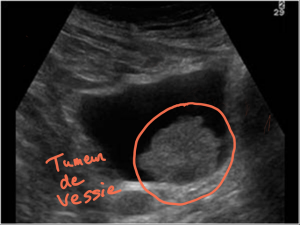

L’échographie

Le principe de l’échographie est l’utilisation d’ultrasons pour permettre de visualiser le contenu des organes abdomino-pelviens.

Elle est utile au titre du dépistage du cancer de la vessie. Elle apprécie la taille de la tumeur et elle peut également apprécier la profondeur de l’implantation de la tumeur dans la paroi vésicale ou l’extension aux organes de voisinage.

Au cours de l’examen, l’étude des reins est réalisée, elle peut permettre de détecter une distension des cavités rénales et un retentissement de la tumeur vésicale.

Cet examen est utile au titre du dépistage surtout. Il est facile à réaliser et à obtenir et il n’y a pas d’utilisation de rayons X.